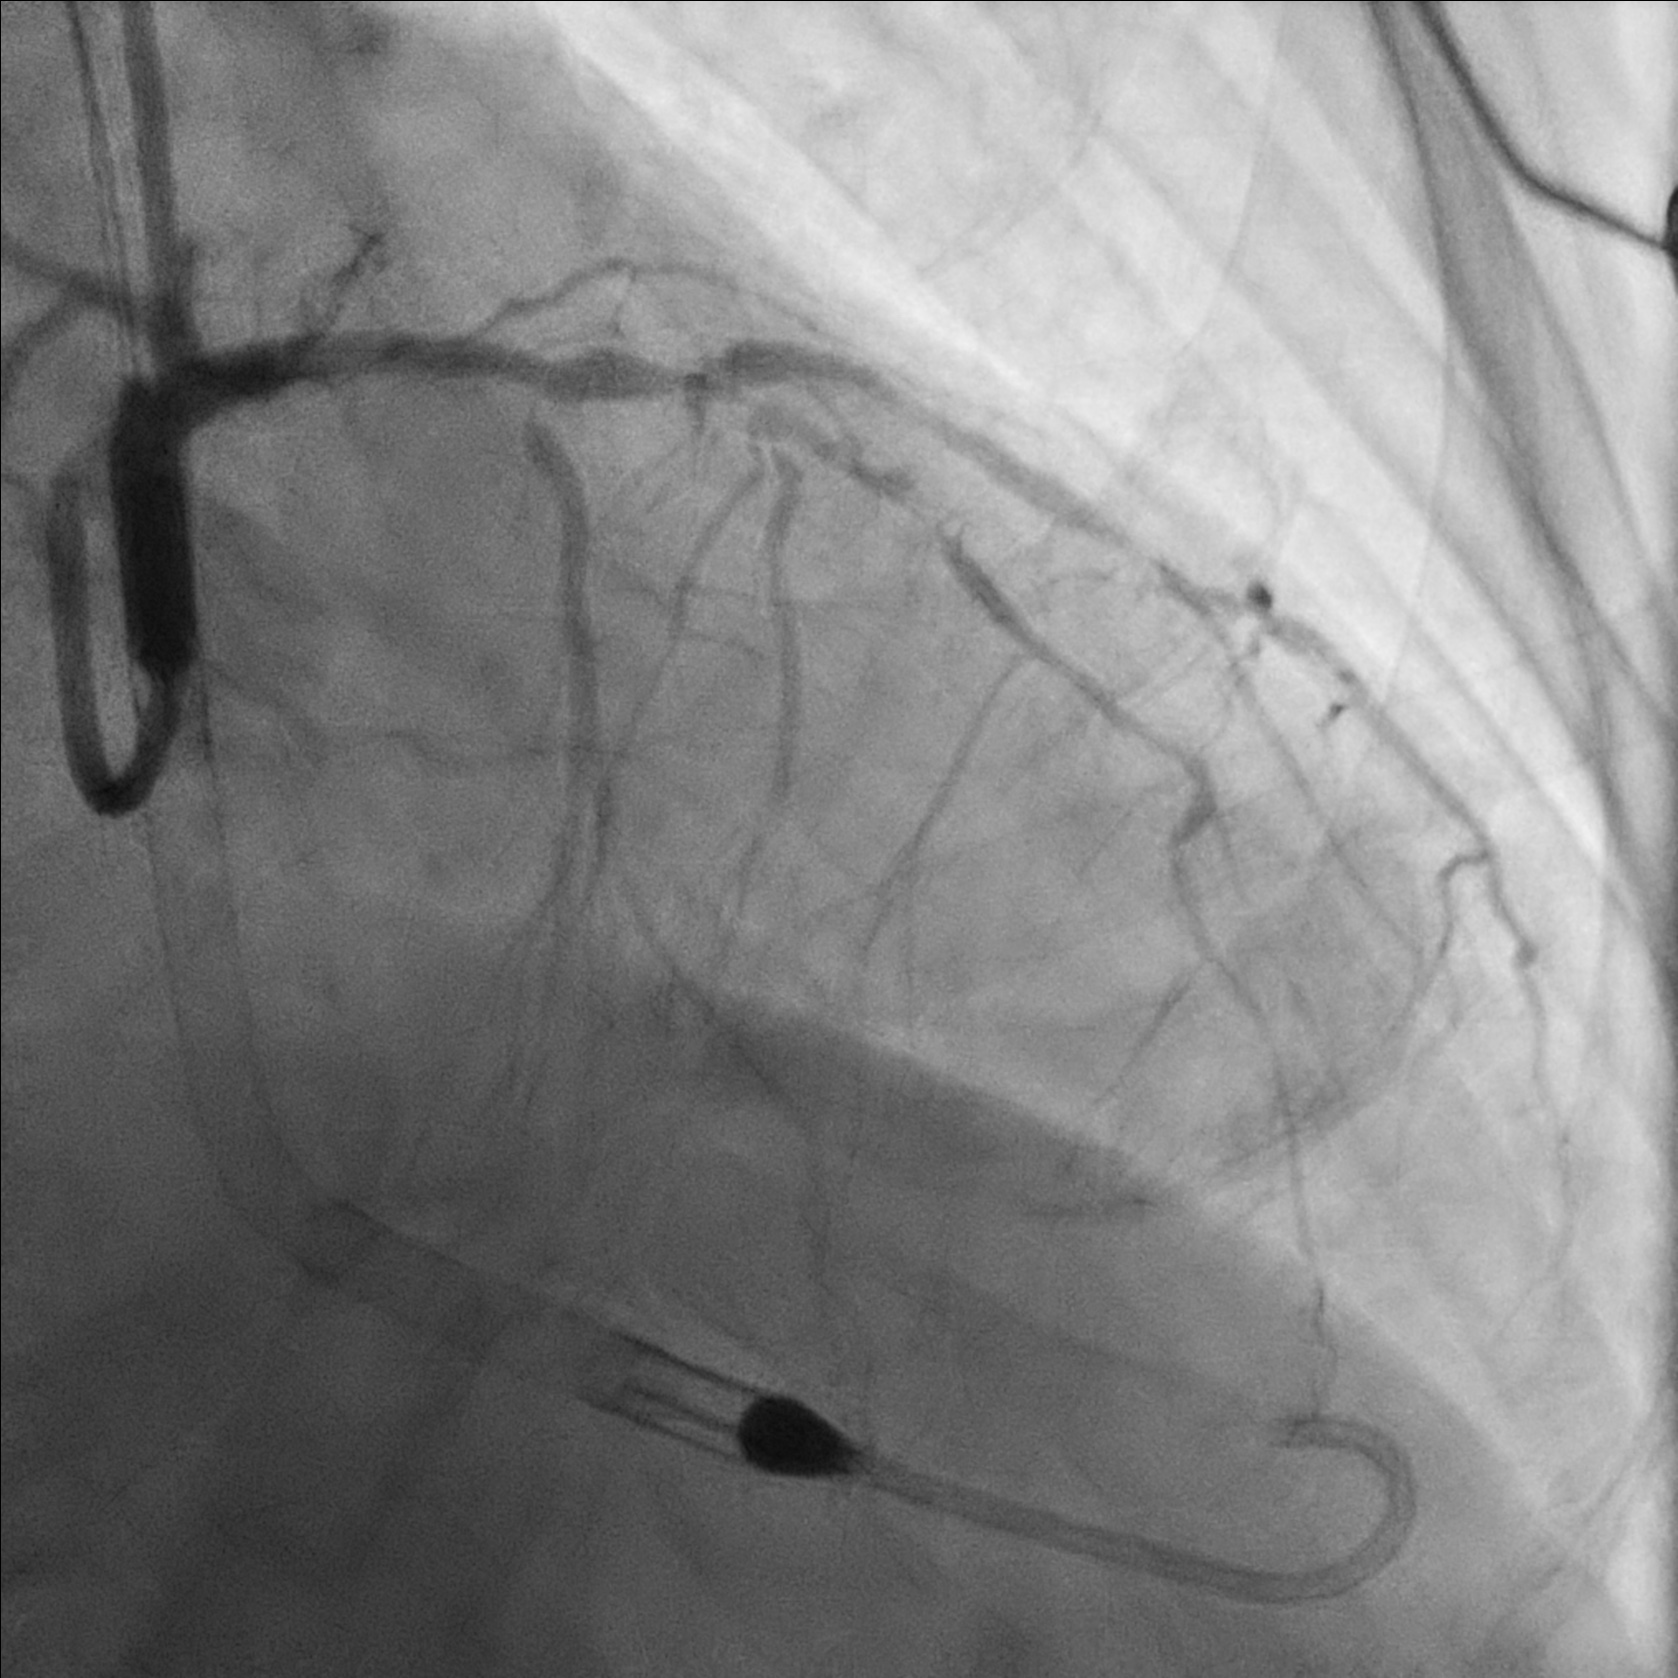

7Fr sheath inserted to right femoral artery. RCA engaged with F7 AL1. Attempted wiring with UB3, Fielder XT-A, Gaia Next 2 and Gaia Next 3. Finally successful RCA wiring with Gaia Next 2 by parallel wire technique. Predilation with Scoring balloon. IVUS showed true lumen wiring. A 3.5/50 DES was deployed over m-dRCA, another 4.0/38 DES was deployed over p-mRCA.